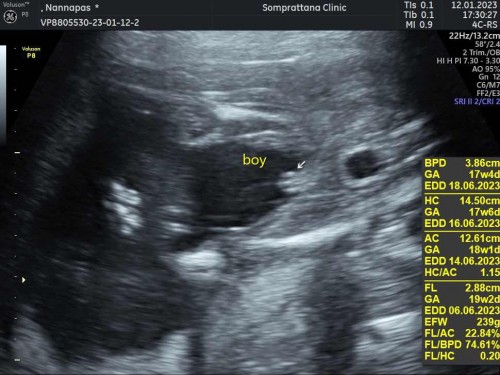

ช่วยดูหน่อยว่าเพศชาย หรือ หญิงคะ

ป้าหมอบอกเป็นผู้ชาย น้องมีจุจู๋ ..แต่แม่มองดูว่าเป็นกลีบนะคะ ใครพอมีภาพ เปรียบเทียบให้ดูบ้างคะ หรือว่าน้องจะเป็นผู้ชายจริงๆ😅😅

จู๋100%ค่ะแม่ โชว์แบบชัดเจนมาก บ้านนี้ก็ผช.นะคะแต่ไม่ค่อยอ้าโชว์ให้เห็นชัดๆเหมือนในภาพเลย 😂

ผู้ชายจ้า